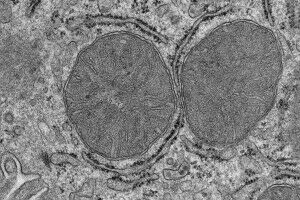

Life Sciences - 25.04.2024

What happens in the body when we are hungry and see and smell food? A team of researchers at the Max Planck Institute for Metabolism Research has now been able to show in mice that adaptations in the liver mitochondria take place after only a few minutes. Stimulated by the activation of a group of nerve cells in the brain, the mitochondria of the liver cells change and prepare the liver for the adaptation of the sugar metabolism.